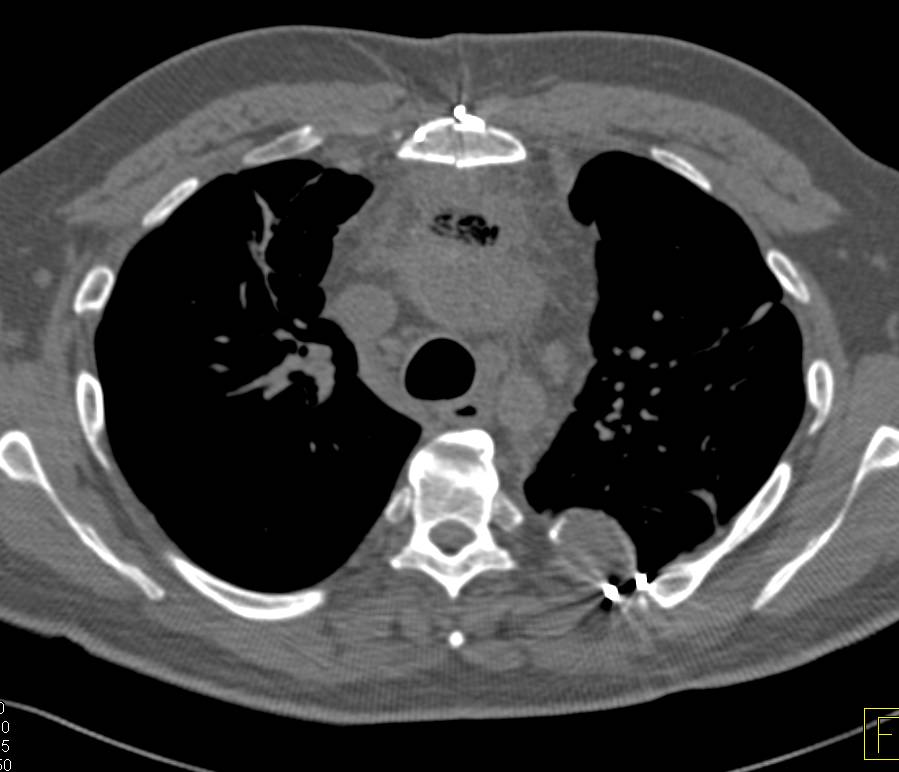

CTA of Aortic Valve Replacement (AVR) Repair and Normal Carotids with a Single Flash Acquisition